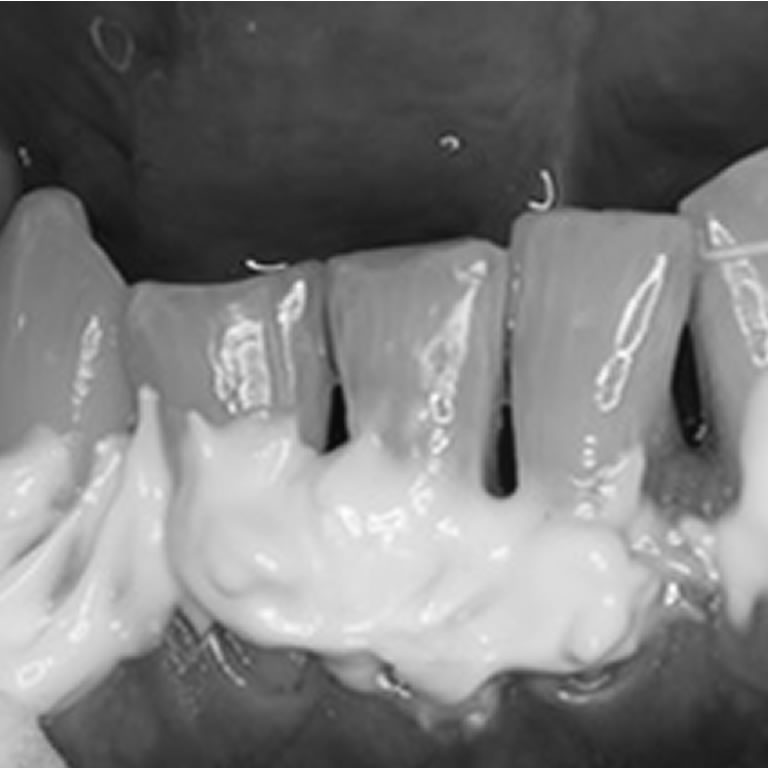

Hiperestesia Dentinaria

Dres. Nélida Cuniberti y Guillermo Rossi.

a hiperestesia dentinaria es una sensibilidad dental caracterizada por dolor breve ante estímulos como frío, calor, presión o ácidos, debido a la exposición de la dentina. Su correcto diagnóstico y tratamiento pueden reducir molestias y mejorar el confort bucal.